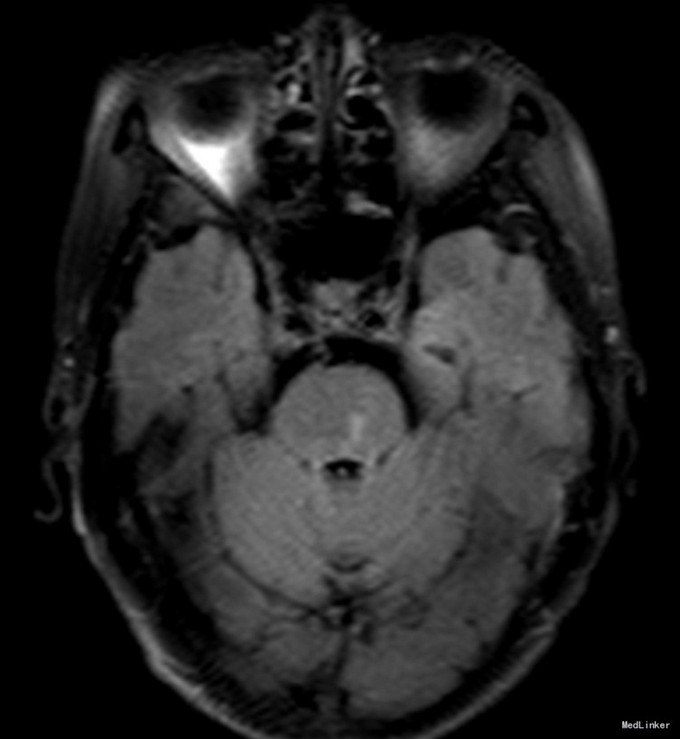

老年女性,急性起病。查体可见左眼内收受限,双眼右视时有水平眼震。影像学提示左侧桥脑背侧梗塞。与临床相符。考虑前核间性眼肌麻痹。 附上另一例前核间性眼肌麻痹头MRI,如图: